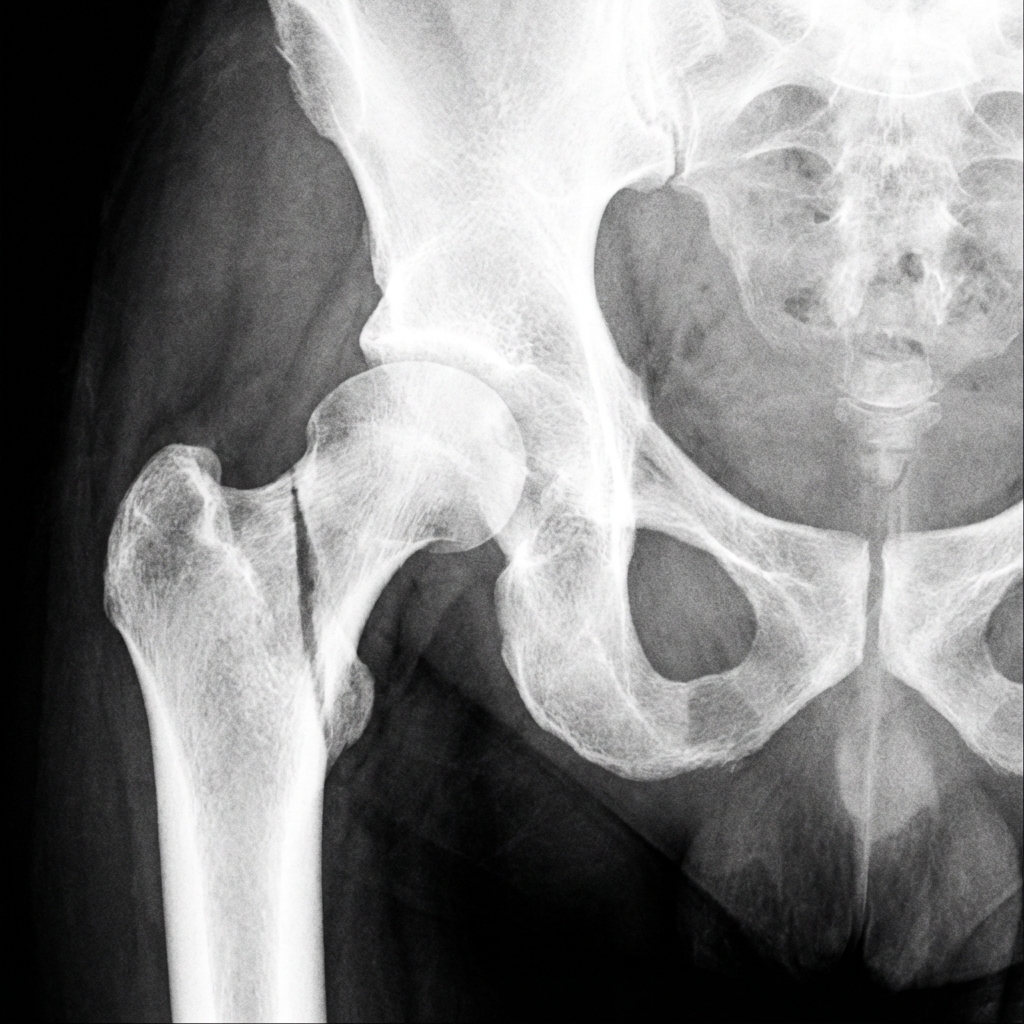

AP pelvis radiograph demonstrating displaced subcapital femoral neck fracture (Garden IV) in a young adult. The femoral head is completely displaced with no contact between head and neck fragments. High Pauwels angle (>70°) indicating high shear forces. This is an orthopaedic emergency requiring urgent anatomic reduction and fixation.

Image source: Open Access medical literature (NIH/PubMed Central) • CC-BY License